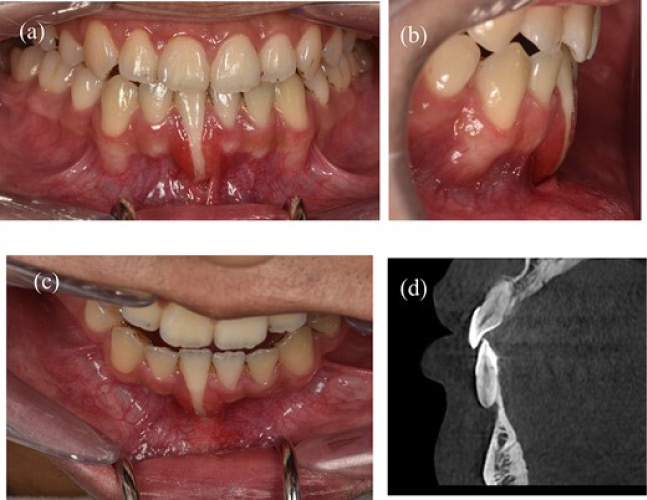

A 22-year-old male patient exhibited an isolated buccal recession of Class I Cairo [5] on tooth 41, showing indications of significant inflammation in the marginal soft tissue. The patient had received a comprehensive orthodontic treatment 2 years ago. During the initial examination, there was a fixed lingual retainer extending from tooth 34 to tooth 44. The patient initially reported no recession of 41 after orthodontic treatment, but one year later, the recession appeared and became more serious after that. A fixed retainer can cause side effects on the teeth if it is not passive, leading to an undesirable force system and moment in the labial-lingual side (Fig. 1b) where the torque of tooth 41 showed a significant difference compared to other teeth. The periodontal assessment indicated the presence of a thin gingival phenotype, and a marginal tissue recession that exhibited a depth of ~9 mm, a width of 3 mm, and attached gingiva was absent. The measurement of marginal tissue recession was noted as the distance from the cemento- enamel junction to the tissue margin (Fig. 1a–c). Panoramic and cone beam computed tomography assessments were conducted. In the sagittal cross-sectional view of the cone beam computed tomography (CBCT) scan, the tooth exhibited malpositioning, extending beyond the dental alveolar bone (Fig. 1d).

Figure 1: A 22-year-old man exhibits gingival recession in the lower left central incisor. (a) Intraoral image illustrating the labial view. (b) Intraoral image illustrating the lateral view. (c) Intraoral image illustrating the bird’s-eye dental view. (d) CBCT radiograph capturing the recession region.